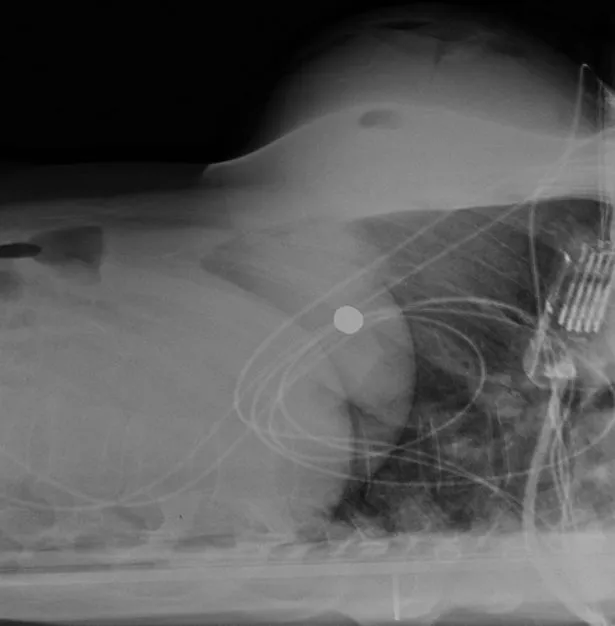

A golyó eredetileg a mellkasán keresztül egyenesen a szívéig hatolt volna, szinte semmi esélye sem lett volna a túlélésre. Igen ám, de a beültetett szilikonpárna felfogta a golyót, így az egyetlen létfontosságú szervet sem érintett, és végül a nő jobb oldalába fúródott.

„A bal mellbe ültetett implantátum megváltoztatta a golyó röppályáját. Ugyan valóban a bal oldalon fúródott be, a szilikonnak köszönhetően a szegycsontján keresztül jobbra vándorolt, ott végül az egyik bordáját találta el, ami el is tört” – ecsetelte Giancarlo McEvenue sebész, a nő kezelőorvosa.